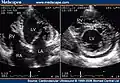

Transthoracic two-dimensional echocardiogram in apical four chamber and parasternal short axis at the level of both ventricles demonstrate dilatation, deep trabeculae and intertrabecular recesses in the inferior, lateral, anterior walls, middle and apical portions of the septum and apex of the left ventricle. [3] -